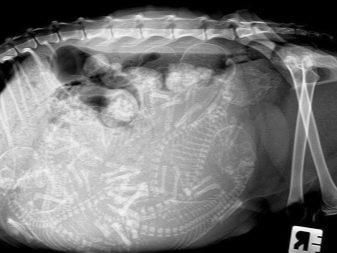

Pokud byly všechny předchozí body úspěšně dokončeny a nový pár zraje, aby vytvořil kočičí rodinu, začne kočičí březí proces. Tento proces je pomalý a vyžaduje trpělivost a zvláštní péči, a to nejen pro samici, ale také pro její budoucí potomky. Období těhotenství exotiků je až 65 dnů plus nebo mínus 1-2 dny. Je třeba poznamenat, že koťata, která se narodila mezi 50–58 dny, obvykle umírají okamžitě.